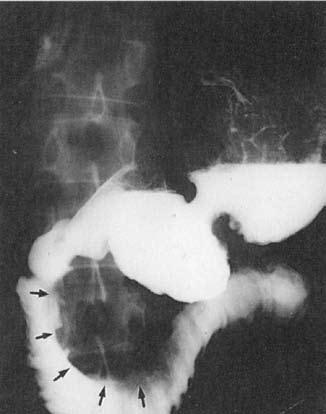

При рентгенографии желудка исключаются его органические поражения, могущие иметь отношение к патогенезу панкреатита, и иногда выявляются деформации, связанные с изменениями в ПЖ, например, вдавления при наличии псевдокист, опухолевидной формы ХП и т. д. (рис. 134).

Рис. 134. Деформация контура выходного отдела желудка и разворот двенадцатиперстной кишки при кисте головки ПЖ

Дуоденография дает возможность судить о свободном пассаже бария через двенадцатиперстную кишку или же о наличии дуоденостаза, как уже упоминалось, имеющего значение в патогенезе ХП. Информативным методом является рентгенологическое исследование двенадцатиперстной кишки в условиях медикаментозной (искусственной) гипотонии, достигаемой предварительным введением спазмолитиков, например, атропина. Характерными признаками ХП, выявлению которых способствует гипотония, является расширение подковы двенадцатиперстной кишки вследствие увеличения размеров головки поджелудочной железы, наличие на медиальной стенке нисходящего отдела кишки широкого дефекта наполнения, иногда стенозирующего просвет и затрудняющего пассаж бария (рис. 135).

Рис. 135. Дуоденография с гипотонией. На снимке видно расширение подковы двенадцатиперстной кишки и сдавление кишки на уровне нисходящей и нижней горизонтальной ее ветвей увеличенной головкой поджелудочной железы